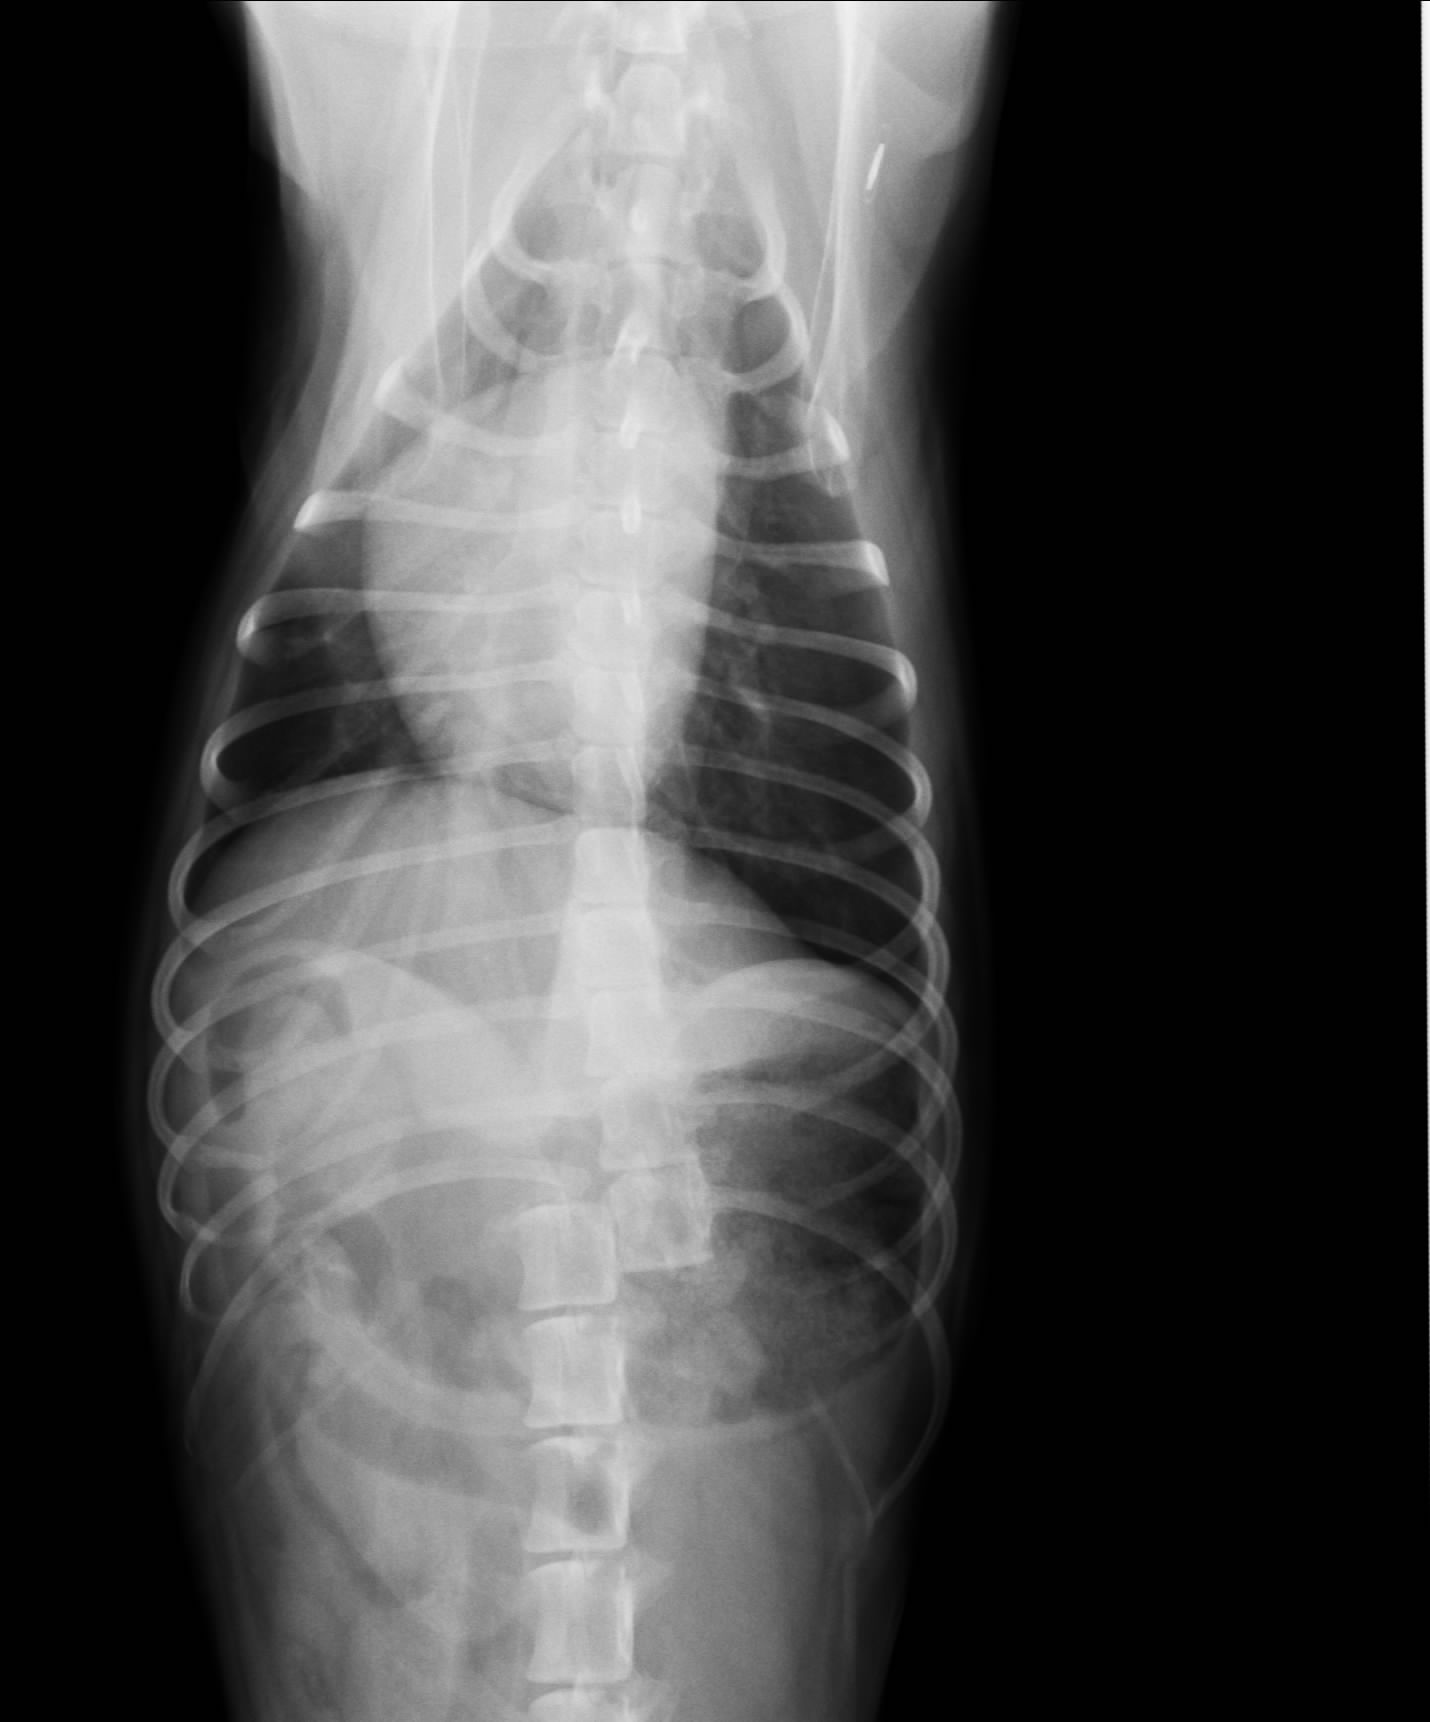

来院時、大きな外傷はありませんでしたが、両方の後ろ足が麻痺していました。まさか!と思いましたが、各種検査の結果、脊椎(背骨)が途中で脱臼していました。(画像をクリックで拡大になります。)

つまり脊髄神経が途中で切断されてしまっていると言うことになります。よって後ろ足(下半身)は回復の見込みはきわめて低い状態ということになります。

幸いなことに、レントゲンを撮影時にマイクロチップを発見!リーダーで読み取り、ネットで本来の飼い主様を探し出すことに成功。